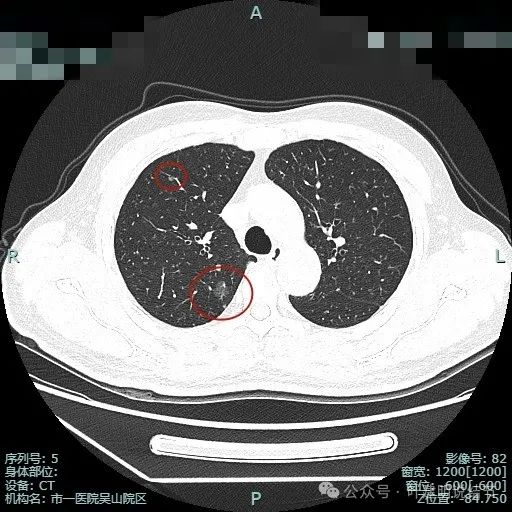

先来看两肺多发结节的总体情况:

病灶1:左上叶肺尖淡磨玻璃影,轮廓稍显模糊,少许慢性炎或肺泡间隔增宽可能性大。

病灶2:右上肺胸膜下微小磨玻璃结节,表面欠光滑,倾向肺泡上皮增生之类的病变,目前不十分确切,但风险总是低的。

病灶3:右上叶点状偏高密度微小结节,只有1毫米许,无法定性,但增殖灶的可能性大点,因为密度感觉稍显高。

病灶4:左上叶点状高密度结节,良性可能性较大。